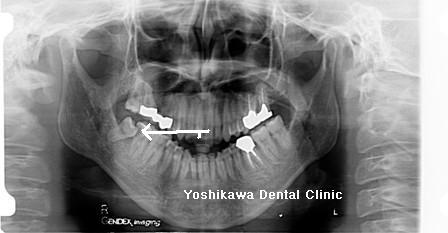

レントゲンです。

親知らずが手前の歯にくいこんでいます。

手前の歯は思ったより思ったより虫歯が進行していたので残せるかどうか微妙です。